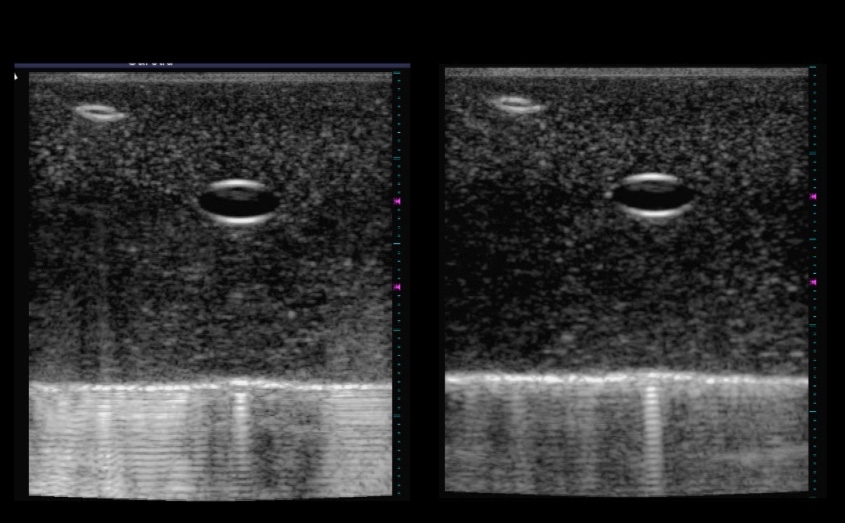

Two black and white images with two bubbles toward the top

Ultrasound images, known as sonograms, have become a familiar part of pregnancy, allowing expectant parents a view of their unborn child. But new research at MIT could improve the ability of untrained workers to perform basic ultrasound tests, while allowing trained workers to much more accurately track the development of medical conditions, such as the growth of a tumor or the buildup of plaque in arteries.

There are two key elements to the improvements engineered by Anthony and his team. First, the researchers devised a way to adjust for variations in the force exerted by a sonographer, producing more consistent images that can compensate for body motions such as breathing and heartbeat. Second, they provided a way to map the exact location on the skin where one reading was taken, so that it can be precisely matched with later readings to detect changes in the size or location of a tumor, clot or other structure.

Anthony likens that precise positioning to “an on-the-patient GPS system” for locating structures in the body. The ability to take images over time from exactly the same position makes it possible to monitor changing tissues quite precisely: The imaging system can determine the volume of a near-surface tumor or other feature to within an accuracy of 1 to 2 percent, he says. There are existing ways to get this kind of accuracy, but these require expensive specialized equipment that few hospitals have.